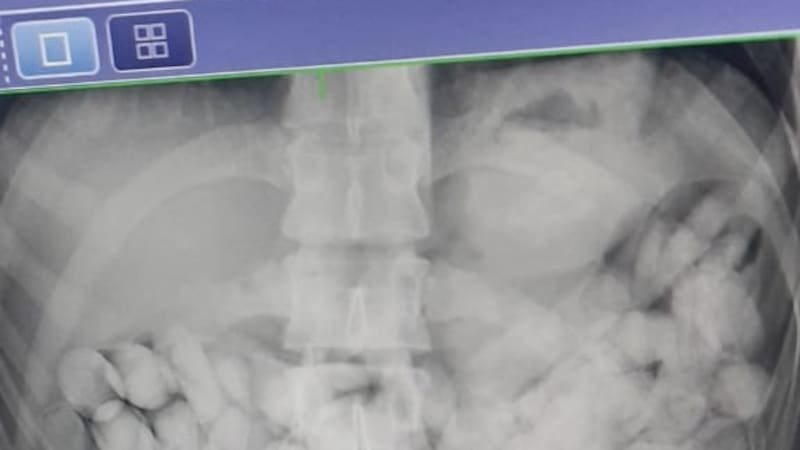

Un policía le preguntó a Chuyuca si le podían hacer un escáner de rayos X. Él aceptó. El resultado sorprendió a todos: la imagen que entregó la máquina mostraba montones de ovoides dentro de su cuerpo. Estimaron que más de cien, y eso era raro: Chuyuca era una persona de estatura mediana y contextura delgada.

Chuyuca fue trasladado al Hospital Regional de Arica. Ahí, después de un nuevo examen, el médico de turno confirmó a las 2.50 que había cuerpos extraños dentro del imputado. Con el pasar de las horas, los policías fueron entendiendo otras cosas. Chuyuca no declaró, pero sí empezó a cooperar con información. Confesó que portaba droga y que la tragó horas antes en Tacna.

Una hora y 55 minutos después de llegar al hospital, Chuyuca defecó los primeros 38 ovoides. Luego de analizarlos, confirmaron que portaban ketamina. El imputado siguió retenido en el hospital. Cada cierto tiempo iba al baño y expulsaba más cápsulas. Cada huevo que botaba contenía casi 10 gramos de droga.

Cuando terminó, la suma final sorprendió a la policía y a la Fiscalía: eran 221 ovoides con ketamina. En total, dos kilos 150 gramos: $ 43 millones en valor de mercado.

Una última radiografía del 30 de julio confirmó que Chuyuca ya no tenía droga en su interior. Después de eso, quedó detenido e imputado por tráfico de drogas. Cuando le explicaron sus cargos, su estado de ánimo decayó. El subprefecto Quiroz dice que el albañil se desanimó aún más cuando supo que arriesgaba de tres a cinco años de presidio efectivo.